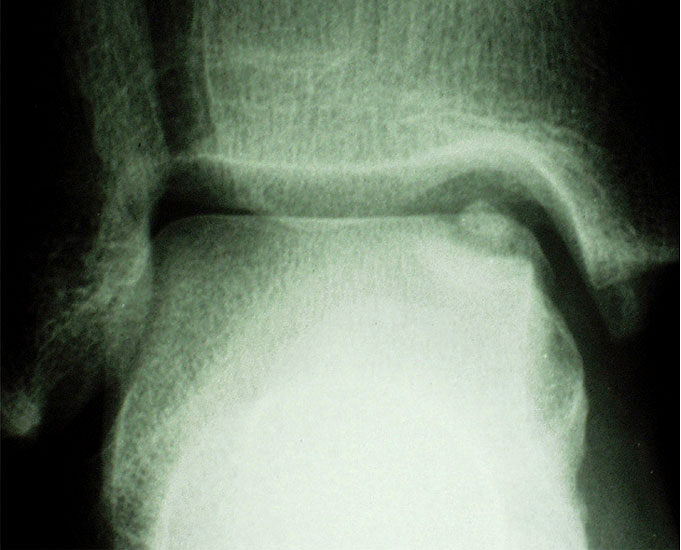

Laterale Läsionen entstehen meist durch ein akutes Trauma mit dorsalflektiertem und invertiertem Sprunggelenk, was zum Anschlag des Talus an der Fibula führt. Diese Läsionen sind meist vorderen Anteil der Talusrolle zu finden 7. Mediale Läsionen sind eher mit wiederholten Supinationtraumata verbunden oder treten aus ungeklärter Ursache auf. Insgesamt sind mediale Läsionen häufiger und meist im mittleren und hinteren Drittel des Talus zu finden 7. Laterale Läsionen sind von ihrer Konfiguration her eher flach und „waffelförmig“ (wafer-shaped) (Abb. 1), während sich mediale Läsionen eher tiefer und „tassenförmig“ (cup-shaped) darstellen (Abb. 2).

Röntgen

Die konventionell im Stehen durchgeführte Röntgenaufnahme des oberen Sprunggelenkes in zwei Ebenen (a.p. mit 20° Innenrotation und seitlich) steht am Anfang der bildgebenden Diagnostik. Die Röntgenaufnahme besitzt allerdings für die sichere Detektion einer Läsion, insbesondere bei geringgradigen oder kleinen Läsionen, eine geringe Sensitivität mit Raten nicht-diagnostizierter Läsionen von bis zu 41% 18.

Bei Fußdeformitäten oder Achsabweichungen sollten weitere Aufnahmen (z.B. Ganzbeinstehaufnahme, Rückfußaufnahme (Saltzman view), ganzer Fuß in zwei Ebenen im Stehen, angefertigt werden um evtl. ursächliche Pathologien besser beurteilen zu können. Posteromediale oder posterolaterale Defekte werden evtl. erst durch eine Spezialaufnahme mit 4mm Fersenerhöhung und Plantarflexion sichtbar 18. Anterolaterale Läsionen, welche häufig bei Akuttraumata anzutreffen sind, können besser in leichter Dorsalextension eingesehen werden 19.